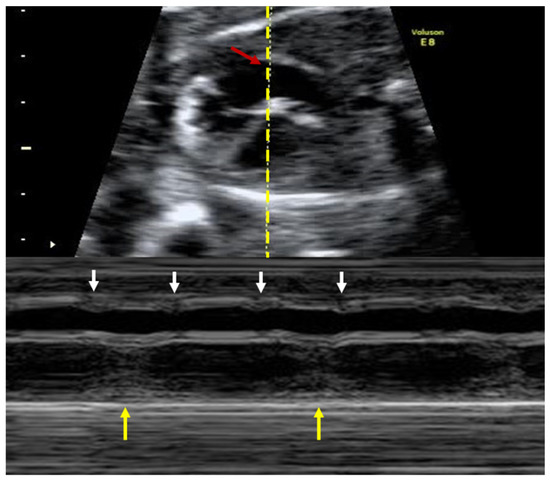

A 28-year-old completely asymptomatic female at 23-weeks gestation was admitted for further investigations regarding a recently diagnosed third-degree AV fetal block, on a routine obstetrical visit. The total dissociation between the atrial and ventricular activity is best demonstrated by the use of M-mode echocardiography, which simultaneously records the atrial and ventricular contractions (see Figure 6).

Figure 6.

M-mode echocardiography used to demonstrate the fetal third-degree atrioventricular block. The atrial and ventricular activities are completely dissociated. Red arrow, dotted yellow line: section plane. Small white arrows: ventricular contractions. Large yellow arrows: atrial contractions. Courtesy of Anca Panaitescu, Filantropia Clinical Hospital, Bucharest.